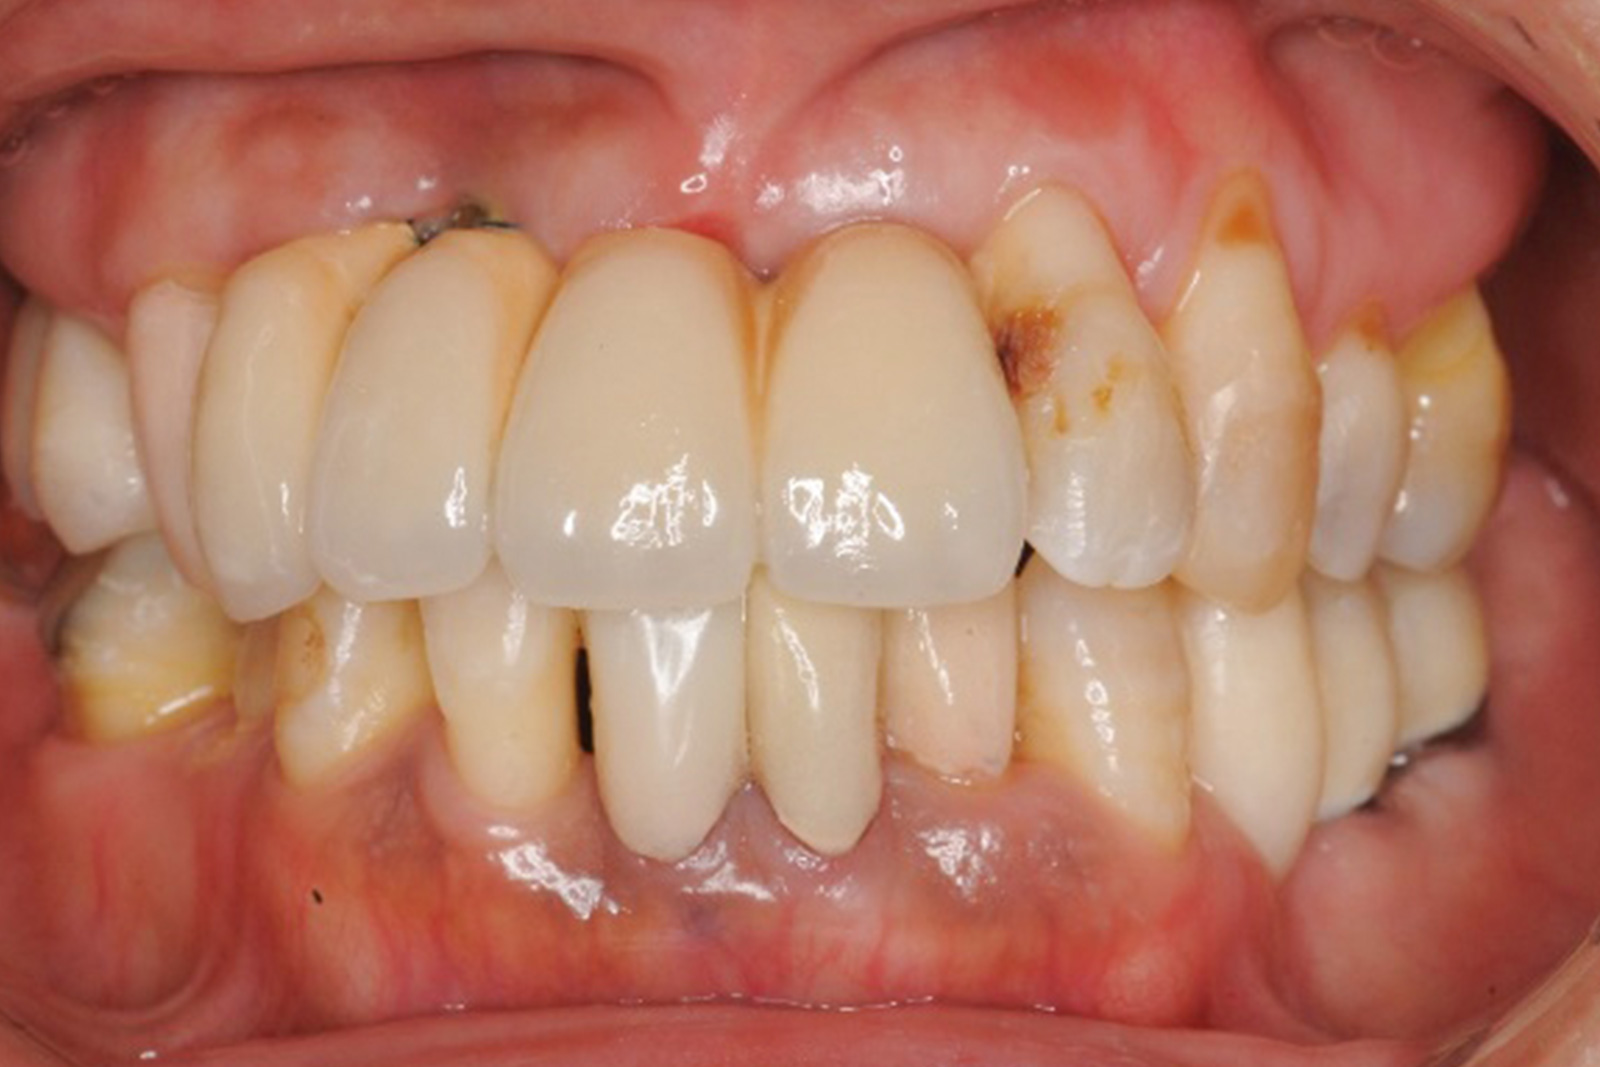

当院がこれまで、どのような症例を手がけてきたのか。その一例を紹介します。

歯や歯茎、歯を支える顎の骨までも含めた口の中全体を整える治療は非常に難しく、緻密な治療計画と確かな技術が求められます。

歯がボロボロになり崩壊した口の中を改善し、見た目も整えるために、当院では歯科の各分野の専門家がチームを組み、さまざまな手法を使って治療を進めます。